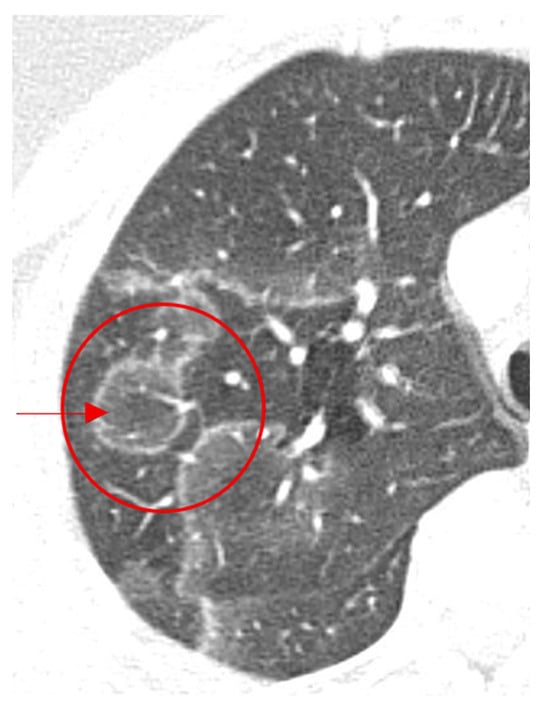

Cosmic Signs in Radiology: A Pictorial Review

Pattern recognition remains a cornerstone of radiologic interpretation, as it facilitates a confident and comprehensive differential diagnosis. Certain pathologies present with specific and highly recognizable patterns on imaging modalities. These patterns can resemble familiar real-life phenomena, including cosmic bodies that surround us. We present in this article a compilation of radiologic signs across various modalities that take inspiration from cosmic phenomena. For each sign, we summarize its defining imaging appearance, typical clinical context, and common pitfalls; where available, we note diagnostic performance (e.g., sensitivity/specificity) to guide appropriate weighting in practice. By coupling memorable imagery with succinct clinical guidance, this pictorial review aims to support a faster, more accurate pattern recognition that is applicable in both low-resource and tertiary care settings, while recognizing that these signs function as educational aids rather than validated diagnostic tests. In familiarizing themselves with these classic signs, training radiologists can benefit from an engaging and memorable way of recognizing various pathological conditions. Full article

Figure 1